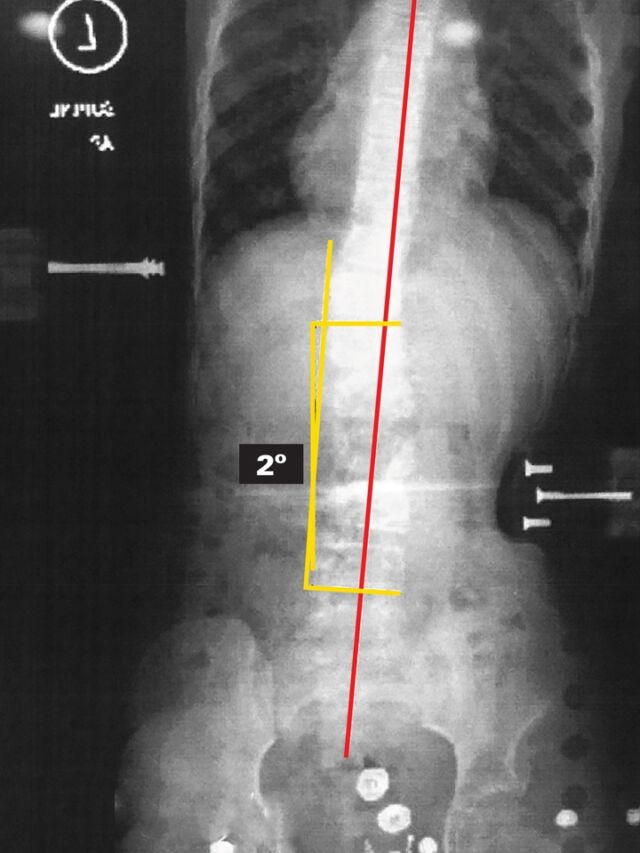

Providence® Brace Correction

The proof is in the correction.

Below are x-ray results of the Providence® orthosis correction on different scoliosis curves.